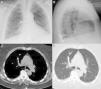

Mujer de 76 años, intervenida 2 años antes por estenosis del canal lumbar quedando con desequilibrio sagital y seudoartrosis lumbar. Ingresó para realización de artrodesis de T10 a S1, con vertebroplastia percutánea de L3. Seis horas después de la cirugía comenzó con disnea, taquipnea e hipoxemia. En la radiografía de tórax (fig. 1A y B) se evidenció un material denso ramificado en campo pulmonar superior, medio e inferior derechos, y en campo medio izquierdo. En la tomografía computarizada (TC) torácica (fig. 1C y D) dicho material ocupaba arterias segmentarias del lóbulo superior, medio e inferior derechos, y del lóbulo superior izquierdo, siendo diagnosticada de embolismo pulmonar por cemento (polimetilmetacrilato). Precisó oxigenoterapia de alto flujo las primeras 24h pudiendo disminuir el aporte de oxígeno hasta su retirada los días siguientes. El embolismo pulmonar por cemento es una potencial complicación tras la realización de una vertebroplastia percutánea, debido a la extravasación del cemento inyectado en la vértebra hacia el sistema venoso paravertebral desde donde puede alcanzar las arterias pulmonares1,2. En los casos asintomáticos o de embolismo periférico se recomienda observación, dejando la terapia anticoagulante, e incluso la embolectomía, para los casos sintomáticos o de embolismo central2.

Radiografía de tórax posteroanterior (A) y lateral (B) con material denso ramificado, en relación con émbolos de cemento, en campo pulmonar superior, medio e inferior derechos, y en campo medio izquierdo. En el corte transversal de la TC torácica (C y D), el mismo material ocupa arterias segmentarias del lóbulo superior derecho.